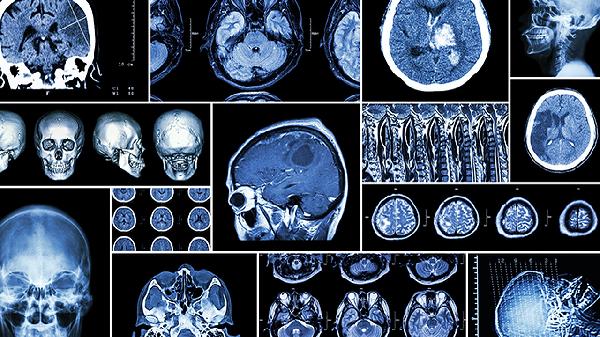

头颅CT是急诊首选检查,发病6小时后可显示低密度梗死灶。弥散加权核磁共振能在发病2小时内检测缺血区域,敏感度超过95%。血管造影可明确闭塞血管位置,CTA或MRA能无创评估脑血管狭窄程度。